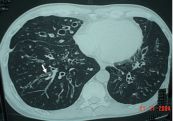

Mức độ nghiêm trọng của chứng giãn phế quản thường được phân loại theo khối lượng đờm nhưng nay phần lớn được thay thế bằng sự xuất hiện dấu hiệu trên CT scan. Cùng tham khảo bài viết dưới đây để hiểu rõ hơn về hội chứng này nhé!